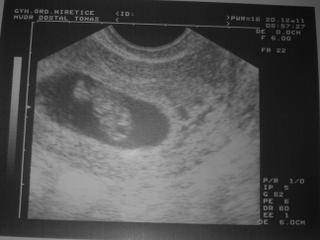

Jinak my holky měříme 17,2 mm, což odpovídá asi 8tt+1. 2. ledna jdu na další utz + ranní moč + krev. Srdíčko nádherně tlouklo, přesto mám v sobě trochu strach, aby to všechno dobře dopadlo. Fotečku přikládám - přijde mi, že už máme malého paňďuláčka - stojí 🙂, je tam hezky vidět i malá ručička.

@petinkas jééééé!!!!!!! Takovou radost mám jsme vážně o den 😀 vy stojíte a my jsme vzhůru nohama 😀 taky to vypadá že jstemalinko doprava, že? jaký Ti řekl dr. termín porodu? já jdu na krev 3. moč jsem nesla dneska ale na další UZ až 17. a budeme měřit šíji 😉 to abysme se rezervovaly společný pokoj 😀